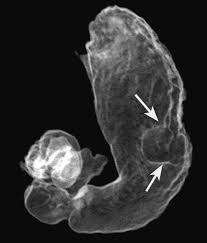

در رادیوگرافی از معده، به بیمار ماده حاجبی به نام سولفات باریم خورانده می شود این ماده سطح داخلی معده را آغشته می کند و در تصویر جدار داخلی معده و احیانا وجود مشکل در این ناحیه دیده می شود. بدیهی است چنانچه معده خالی نباشد تکه های غذایی که به دیواره چسبیده با ضایعات پاتولوژیک (بیماری) اشتباه گرفته می شود.